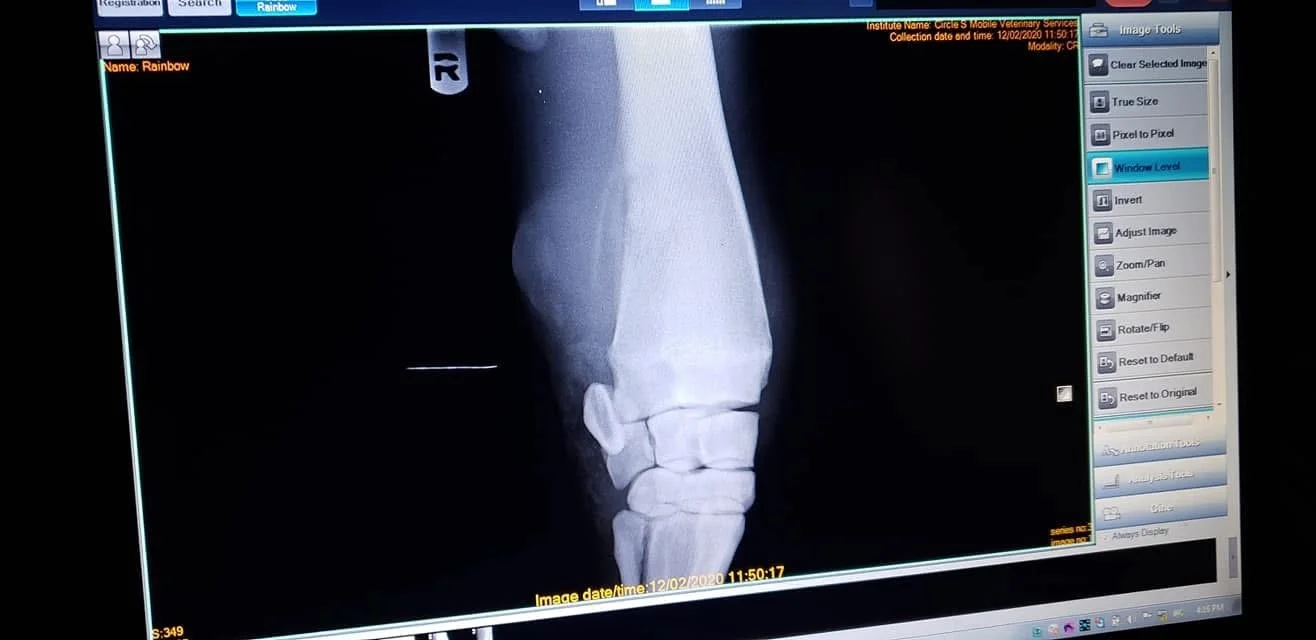

Juneau was saved from the notorious Colorado kill pen (Fabrizius) together with Pedro, River and Dahlia. Jeske reached out to Mountain Shadows Equine Revival based in Laramie, WY to see if they could take in Juneau, as she had a bad bump on her right knee that needed to be seen by a vet asap. The x-rays showed that she would never be sound due to having lost about 80% of range of motion in that joint (right front). Despite this, she is a spunky, happy horse that loves to run and play with other horses. She got very lucky to be adopted by an amazing Wyoming family that were looking for a horse to keep their last senior ranch horse company on their dozens of acres.